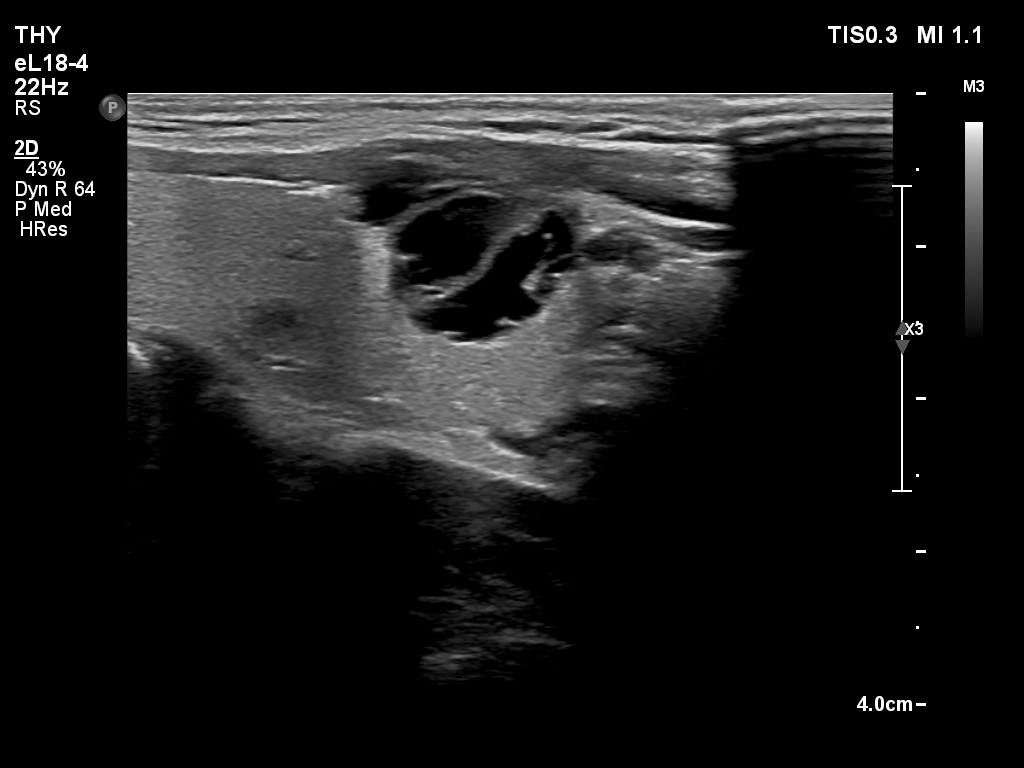

Elastography - case 2178 (ultrasonographic picture 2)

Right lobe, longitudinal scan.